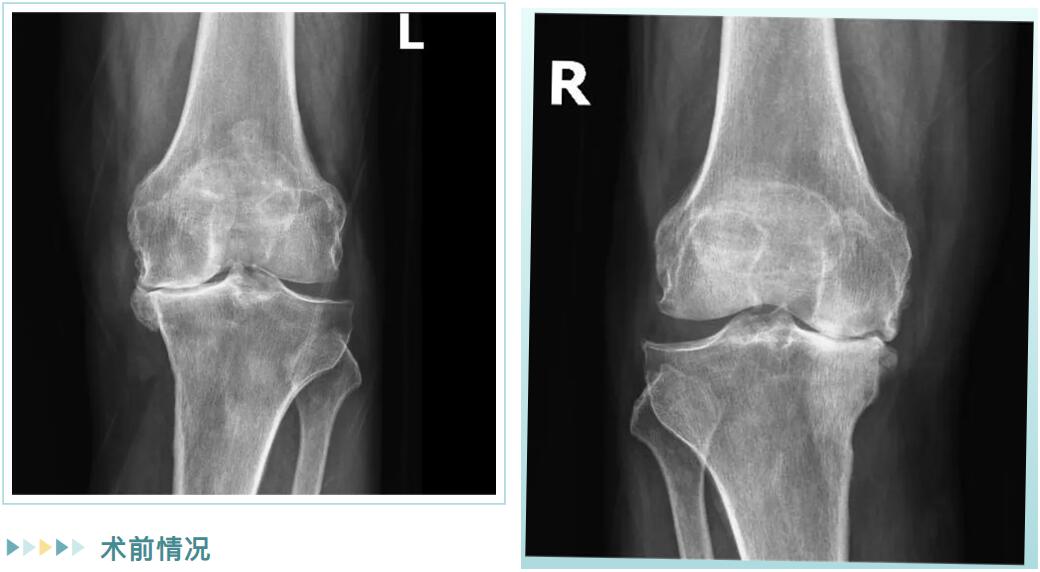

經(jīng)詳細檢查,邵阿伯被診斷為“雙膝重度骨性關(guān)節(jié)炎”。在保守治療無效后,羅院長團隊為他量身定制了治療方案:雙側(cè)膝關(guān)節(jié)內(nèi)側(cè)單髁置換術(shù)。

術(shù)前情況